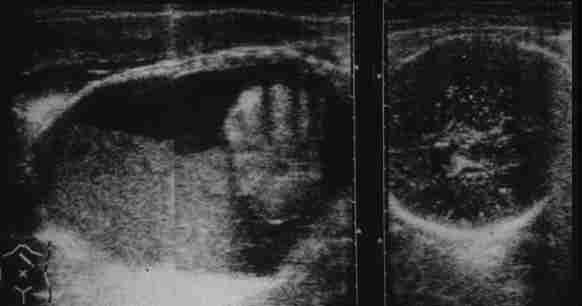

Meconium peritonitis: Several patterns of echography exist.

In

cases with massive meconium ascites and a giant pseudocyst,

respiratory failure may be seen. Maternal transport is desirable.